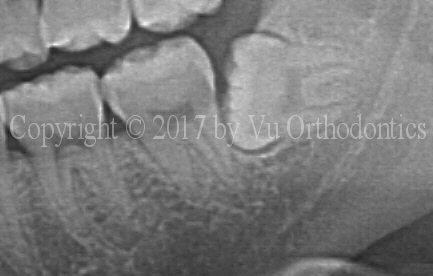

The following example shows a case of an orthodontic patient that needs four premolars extracted. In this case, saving wisdom teeth is the right thing to do. Figure 1 shows an image of impacted wisdom tooth #17.

Fig. 1 Impacted wisdom tooth #17